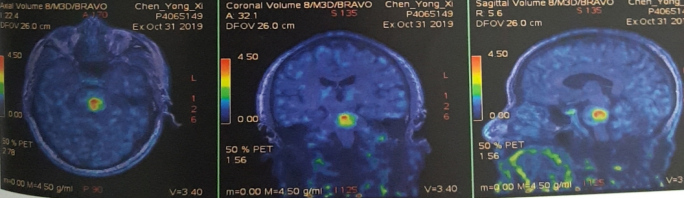

脑部蛋氨酸PET示:脑桥结节,蛋氨酸代谢异常增高,SUVmax 4.51,考虑转移性恶性肿瘤。